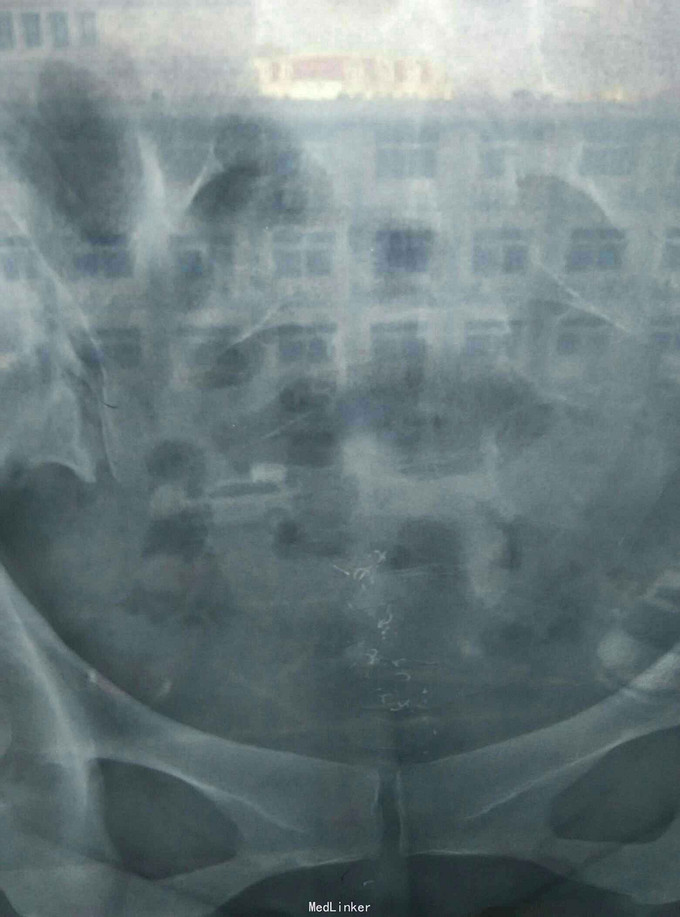

患者一般查体正常,超声检查宫内节育环形状不清楚,放射线小情况如下图,化验检查正常